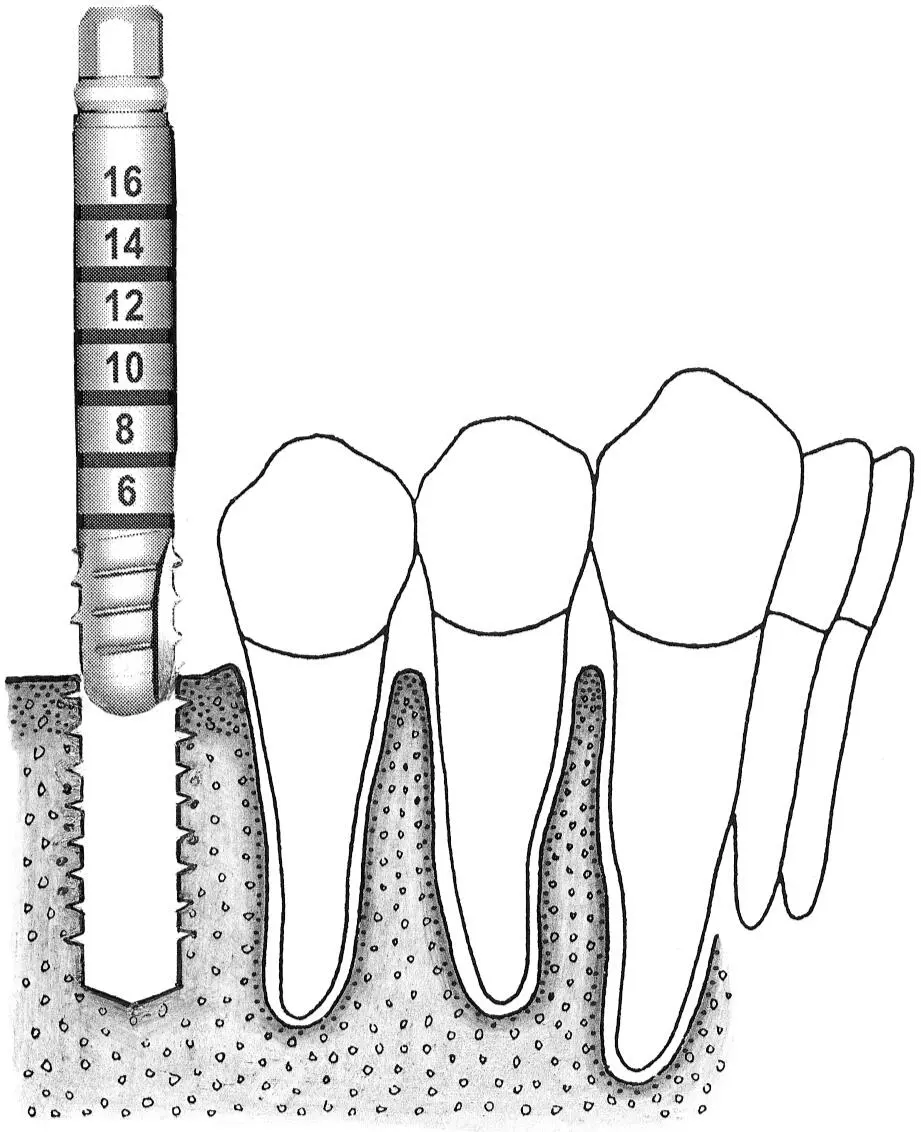

Fig 1-5Varying sink depths.

Fig 1-5a The 3.5-mm-diameter depth gauge is inserted so that the middle of the 12-mm mark is aligned with the bone crest (left) . When the standard implant is inserted, this allows the rough border to be aligned exactly at the crest (right) .